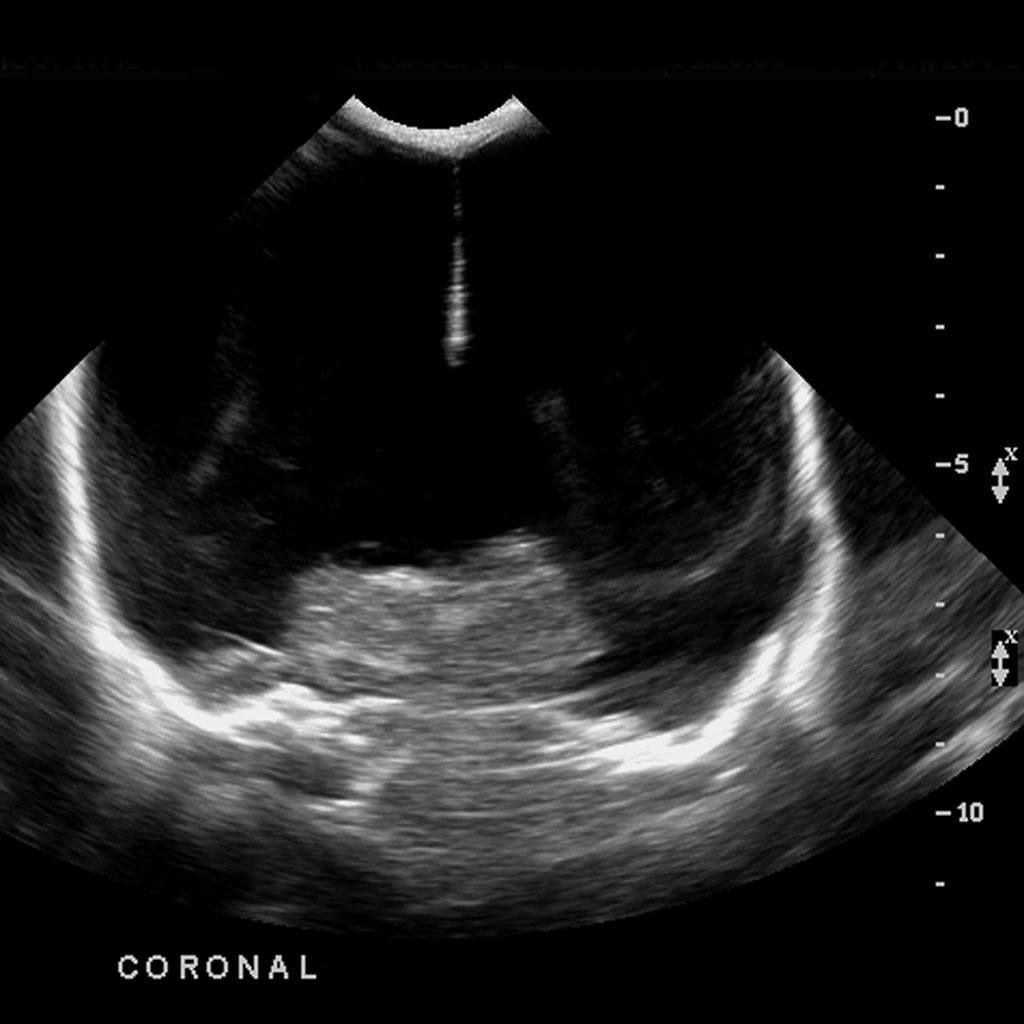

ΔΑΝΕΙΖΟΜΑΙ ΑΥΤΗ ΤΗΝ ΕΙΚΟΝΑ ( http://radiopaedia.org/images/151709) ΑΠΟ ΙΣΤΟΤΟΠΟ ΑΝΘΡΩΠΙΝΟΥ ΑΠΕΙΚΟΝΙΣΜΟΥ ΓΙΑ ΝΑ ΔΕΙΞΩ ΠΩΣ Η ΕΙΚΟΝΑ ΤΗΣ ΥΔΡΑΝΕΓΚΕΦΑΛΙΑΣ ΜΟΙΑΖΕΙ ΣΤΟΝ ΥΠΕΡΗΧΟ ΣΕ ΑΥΤΟ ΤΟ ΠΕΡΙΣΤΑΤΙΚΟ.

ΣΤΟΝ ΙΣΤΟΤΟΠΟ ΑΥΤΟ ΠΕΡΙΓΡΑΦΕΤΑΙ Η ΕΙΚΟΝΑ ΤΗΣ ΥΔΡΑΝΕΓΚΕΦΑΛΙΑΣ. Ο ΕΓΚΕΦΑΛΙΚΟΣ ΙΣΤΟΣ ΑΝΤΙΚΑΘΙΣΤΑΤΑΙ ΑΠΟ ΕΓΚΕΦΑΛΙΚΟ ΥΓΡΟ.